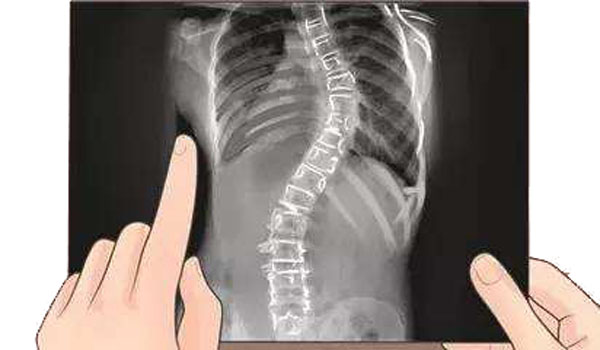

强直性脊柱炎引发脊柱侧弯,矫正后增高10厘米分步治疗脊椎病

近日,在北京大学第一院骨科,一名27岁的强直性脊柱炎引起的脊柱侧弯患者,经王宇医生及骨科专家团队的精心治疗,矫正术后挺直脊柱增高约10cm,康复出院。去年7月,王宇大夫也治愈了一位39岁的强直性脊柱炎患者,术后身高增高27cm。患者术前脊柱后凸超过50度,重度贫血,克服了重重困难,通过单节截骨、双侧夹板等手术矫正,同时把侧弯和后凸都矫正了。术后10天行走自如,顺利出院。

据骨科专家王宇介绍,医学上,脊柱侧弯划分为先天性和特发性。先天性的是指脊柱骨性结构发生异常,即出生后即有三角形半椎体、蝶形椎、融合椎、与胸椎相连的肋骨并肋融合等异常结构,导致脊柱发生倾斜,导致侧弯或后凸畸形。特发性脊柱侧弯,脊柱骨性结构基本没有异常,由于神经肌肉力量的失平衡,导致脊柱原来应有生理弯曲变成了病理弯曲,即原有的胸椎后凸变成了侧凸等。另外还有一些特殊疾病也可引起脊柱侧弯,如:小儿麻痹、强直性脊柱炎等。

强直性脊柱炎是一种慢性炎性脊柱关节疾病,病变主要是从髋关节开始,逐渐的向上发展,造成脊柱强直和纤维化,弯腰、行走活动受限,并可有不同程度的损害眼、肺、心血管、肾等多个器官。主要侵犯骶髂关节、脊柱骨突、脊柱旁软组织及外周关节。临床主要表现为腰、背、颈、臀、髋部疼痛以及关节肿痛,严重者可发生脊柱畸形和关节强直。该病损害脊柱并引起脊柱侧弯,表现在: